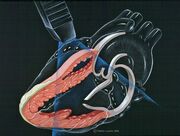

| 06:01, 20 August 2009 | E00108.jpg (file) |  |

189 KB | Secretariat | 1 | |